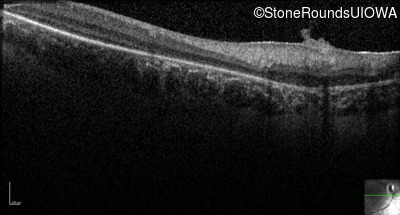

Optical Coherence Tomography - Right - No Light Perception

Exemplar / OCT Stack